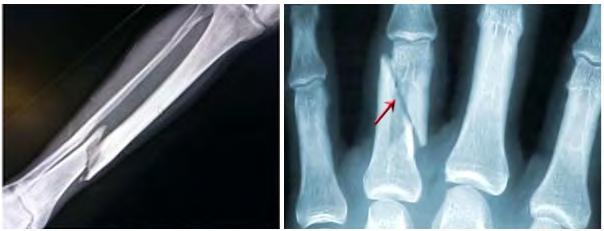

Переломи кісток пов’язані з

їхньої цілісності (іл. 79, б). У разі відкритих переломів уламки кісток проривають шкіру, закритих шкіра залишається цілою. Ознаками перелому є неприродне положення кістки, припухлість і різкий біль. У разі відкритого перелому необхідно

зупинити кровотечу, накласти стерильну пов’язку на рану, а потім знерухомити кінцівку. При закритому переломі знерухомлення кінцівки є першочерговим заходом. Варто зазначити, що у випадку всіх описаних травм необхідно обов’язково звернутися до лікаря. Спроба самостійного лікування може призвести до подальшого травмування організму. Порушення постави. Деякі проблеми опорно-рухової системи можуть розвиватися без зовнішніх впливів. Зокрема, часто трапляються порушення постави. Ви вже знаєте, що лордоз та